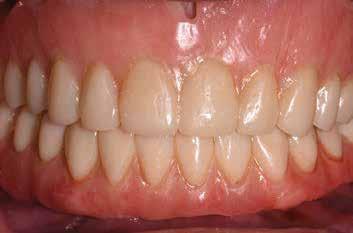

Az azonnali, implantátumokkal megtámasztott teljes íves fogpótlások jól bevált, és egyre inkább elfogadott kezelési módot képviselnek a teljesen fogatlan betegek rehabilitációjában.1,2 Az ilyen típusú helyreállítások esetében átlagosan 5 éves követési időszakban 98%os túlélési arányról számoltak be.3 Az alsó állkapocs kedvező csontminőségnek és anatómiának köszönhetően az azonnali teljes ívek helyreállítása még nagyobb sikerarányt mutatott.4 A digitális technológiák, mint például a sablonnal végzett implantátumbeültetés és a számítógéppel segített protézistervezés és gyártás, képesek megkönnyíteni a diagnózist, a kezelés megtervezését és jelentősen javítják a sebészeti beavatkozásokat, ezáltal kiszámíthatóbb és hatékonyabb kezelést biztosítanak.5,6 Különösen a bonyolult sebészeti eljárások – mint például a teljes ív rekonstrukciója – jelentős mértékben profitálhatnak ezekből az előnyökből, amelyek csökkenthetik a kezelés idejét és az invazivitást a beteg számára.5,7

A digitális technológiákhoz való hozzáférést az anyagi és időkorlátok akadályozhatják, valamint az ilyen technológiákhoz kapcsolódó meredek tanulási görbe.8,9 A közelmúltban a digitális munkafolyamatok elérhetővé váltak egy kihelyezett szolgáltatás részeként: Smile in a Box (Straumann). Ez segíthet a hagyományos munkafolyamatokat használó szakembereknek, hogy könnyen élvezhessék a digitális technológiák előnyeit anélkül, hogy először le kellene küzdeniük az első hozzáféréssel járó akadályokat. Ez az esettanulmány egy hagyományos teljes fogsor sikeres azonnali átalakítását írja le azonnali teljes ívű restaurációvá a Smile in a Box által biztosított kiszervezett, teljesen digitális munkafolyamat alkalmazásával. A Straumann Pro Arch protokoll alkalmazása a Smile in a Box funkcióval kombinálva lehetővé tette számunkra, hogy könnyen hozzáférhessünk egy teljesen digitális munkafolyamathoz, amely hatékonyan integrálható a hagyományos protetikai munkafolyamatunkba, továbbá rendkívül kielégítő klinikai eredményt biztosít.

Klinikánkon egy teljesen fogatlan, hagyományos akrilát fogpótlással helyreállított 65 éves férfi beteg jelentkezett, aki nem kielégítő alsó fogsorretencióra és az azzal járó problémákra panaszkodott, beleértve a kifejezetten az alsó fogsorához kapcsolódó gyenge beszéd és rágásfunkciót. A klinikai vizsgálat gömbölyűtől a késhegyig terjedő mandibulagerinc formát és megfelelő vertikális, de nem megfelelő vízszintes csontmennyiséget állapított meg, különösen a hátsó területen (1. ábra) 10

A hagyományos teljes kivehető fogpótlási technikákkal a kezelési stratégia a felső és alsó állcsont kapcsolatának és az okkluzális vertikális dimenzió és a fog helyzetének meghatározását foglalta magában, majd az alsó rögzített restauráció előállításához ezeket használták fel referenciákként (3. ábra) 11